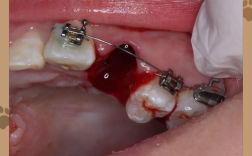

面向口腔医生,直播深入正畸技术的核心细节,如“隐形矫正附件的设计与临床应用”“骨性畸形非手术矫正的适应证与技巧”“数字化取模与方案设计的误差控制”等,曾教授常结合真实病例,从初诊检查、方案制定到治疗过程中的难点突破(如扭转牙纠正、关闭间隙、咬合调整等),逐步拆解操作逻辑,并强调“个性化方案设计”的重要性——例如针对“成人骨性龅牙”,需结合患者面部美学诉求、牙周健康状况,综合选择掩饰性正畸或正畸-正颌联合治疗,而非单一套用模板。

| 技术进阶 | 隐形附件设计、骨性畸形矫正技术、数字化方案设计、并发症处理 | 病例拆解、操作视频、数据图表 | 成人骨性龅牙的掩饰性正畸方案设计;扭转牙纠正技巧 |